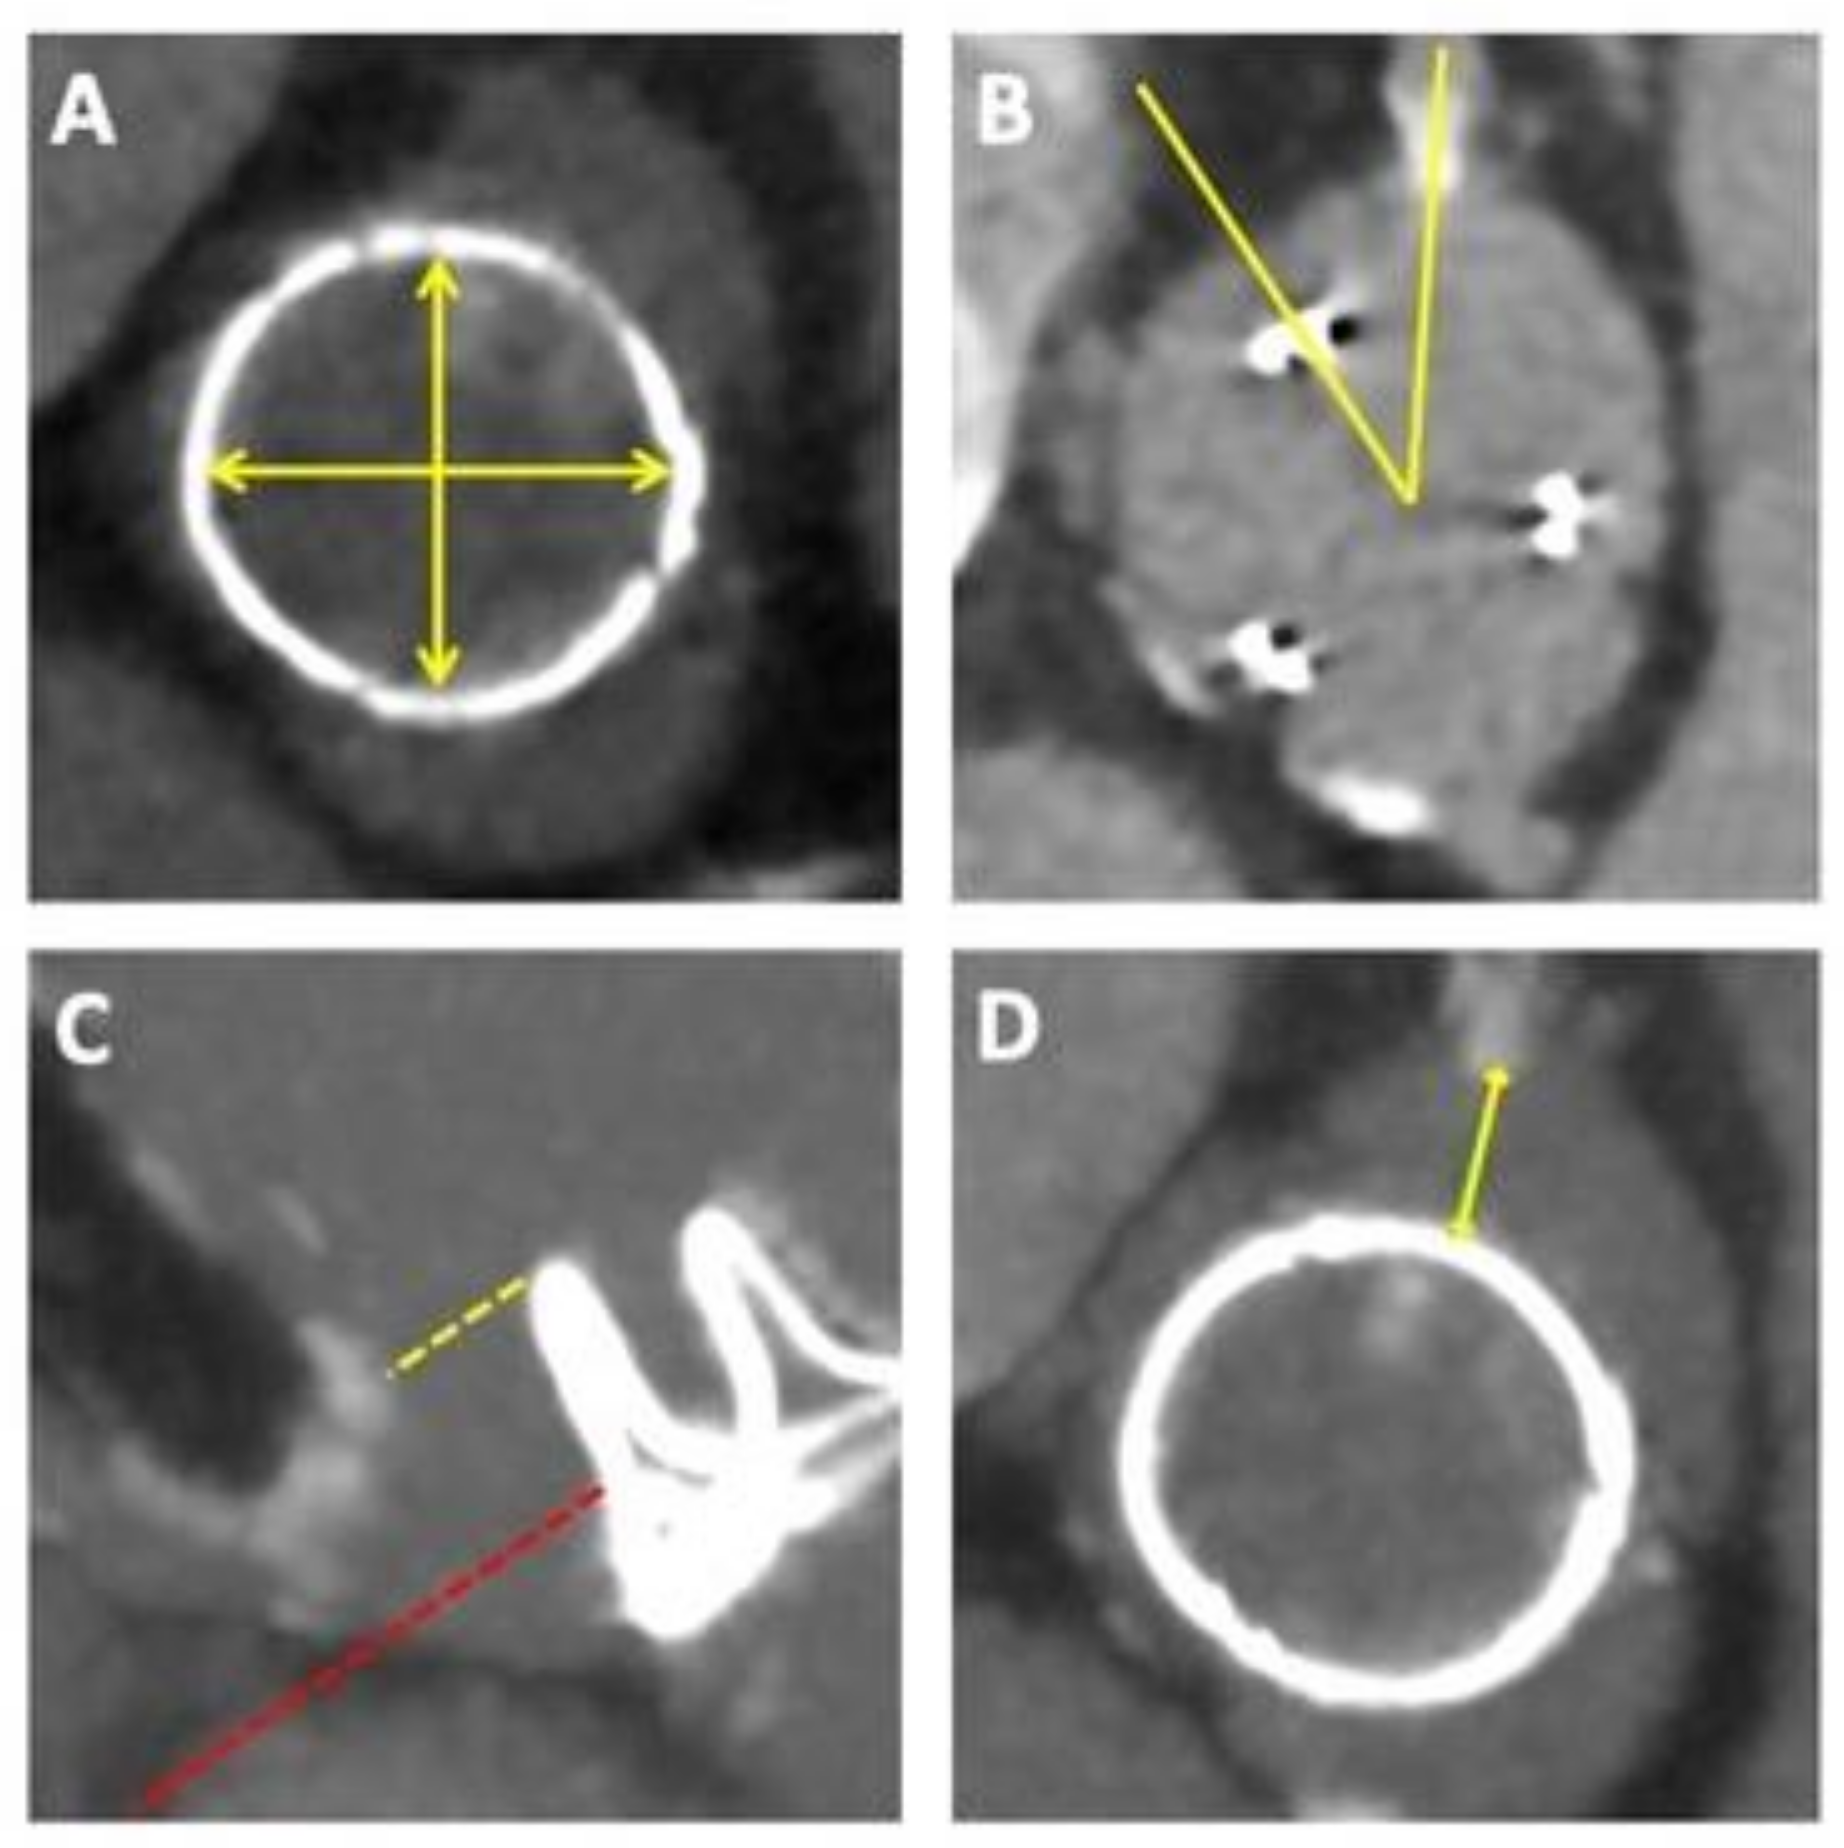

2.1.2. Pre-Procedural Assessment

In addition to understanding the type and size of the implanted bioprosthesis, several other key parameters obtained from the pre-procedural CT are of relevance (Figure 2). Although sizing is generally based on the size and type of the surgical bioprosthesis being treated, precise measurements of the implanted bioprosthesis should be performed to confirm the true ID. In general, it is important to understand and evaluate the relationship between the ViV-TAVI complex comprising the surgical and the transcatheter valves as well as the neoskirt created by the displaced SAV leaflets and the surrounding anatomy, due to the risk of acute or delayed coronary obstruction, which although rare (3–5%) can be fatal [14,15]. The risk of coronary obstruction is greater when treating stentless or stented valves with externally mounted leaflets, using SEV TAVI platforms [15]. The two principal mechanisms underlying coronary obstruction, include direct obstruction of the coronary ostia by the pinned surgical leaflet or indirect obstruction to coronary flow due to sinus sequestration caused by the pinned-up surgical leaflet rising above the sinotubular junction (STJ). In general, the risk of coronary obstruction is greater in narrow and shallow aortic roots where the ViV-TAVI complex lies in close proximity to the coronary ostia. For coronary ostia located above the SAV leaflets the risk of obstruction may be negligible. For coronary ostia arising below the level of the SAV posts or pinned-up leaflets, the distance between the implanted valve and coronary ostia, valve-to-coronary (VTC) becomes relevant. A retrospective evaluation of 37 coronary obstruction cases from the VIVID registry, identified and validated a cut-off VTC measurement of 4 mm to identify those at high-risk for coronary obstruction [14]. A further relevant parameter may be the valve-to-STJ distance (at, as well as, 2 mm above and below the sinotubular junction), with <2.5 mm being considered high risk and a distance between 2.5 mm and 3 mm being considered borderline risk for coronary obstruction [16].

Similar to native-valve TAVI, pre-procedural computed tomography (CT) plays a key role in guiding the selection of THV type, size and implantation strategy [48,50]. Particular attention must be paid to the intended combination and configuration of the valvar complex and its relationship with the surrounding aortic root anatomy to avoid the risk of coronary obstruction or unfeasible coronary access (Figure 4).